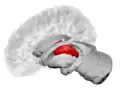

![]() Thalamus marked (MRI cross-section) | |

The thalamus (pl.: thalami; from Greek θάλαμος, "chamber")[1] is a large mass of gray matter located in the dorsal part of the diencephalon (a division of the forebrain). Nerve fibers project out of the thalamus to the cerebral cortex in all directions, known as the thalamocortical radiations, allowing hub-like exchanges of information. It has several functions, such as the relaying of sensory signals, including motor signals to the cerebral cortex[2][3] and the regulation of consciousness, sleep, and alertness.[4]

The thalamus is a paired structure of gray matter about four centimetres long, located in the forebrain which is superior to the midbrain, near the center of the brain with nerve fibers projecting out to the cerebral cortex in all directions. The medial surface of the thalamus constitutes the upper part of the lateral wall of the third ventricle, and is connected to the corresponding surface of the opposite thalamus by a flattened gray band, the interthalamic adhesion. The lateral part of the thalamus is the phylogenetically newest part of the thalamus (neothalamus), and includes the lateral nuclei, the pulvinar and the medial and lateral geniculate nuclei.[6][7] There are areas of white matter in the thalamus including the stratum zonale that covers the dorsal surface and the external and internal medullary laminae. The external lamina covers the lateral surface and the internal lamina divides the nuclei into anterior, medial, and lateral groups.[8]